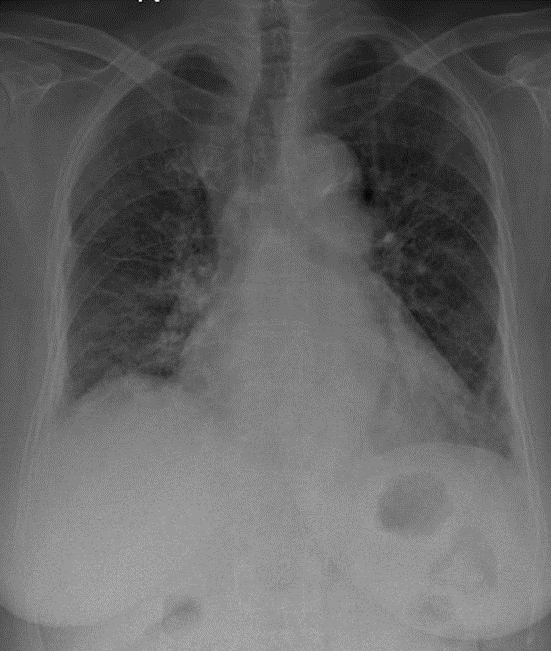

1-Góc carina dãn rộng 2-Xơ rải rác hai phổi 3-Tim to 4-Cung động mạch chủ dãn 5-Cung động mạch chủ đóng vôi